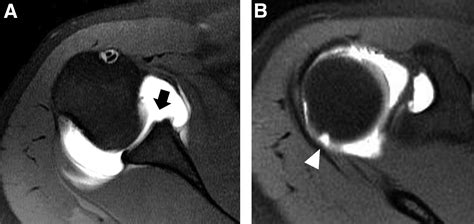

• Imaging studies: X-rays, MRI, or CT scans may be used to visualize the shoulder joint and confirm the presence of a Hill Sachs Lesion. These imaging studies can also help determine the size and location of the lesion, which is important for treatment planning.

In some cases, additional tests, such as arthroscopy, may be necessary to fully evaluate the extent of the injury and plan appropriate treatment.